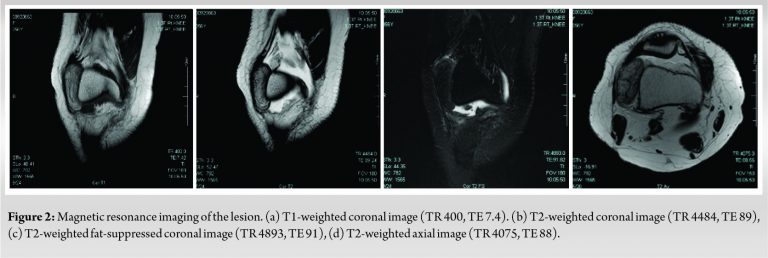

MRI showed an oval-shaped mass of low to high heterogeneous signal intensity on T1- and T2-weighted images at the lateral joint space. Low signal intensity was observed in the fat suppression image (Fig. 2). Therefore, a tumor derived from adipose tissue with fibrous component is suspected.

The mass was 5 cm × 4 cm × 2 cm in size. No contrast agent used.

MRI is an indispensable test for diagnosis of the intra-articular lesions such as synovial lipoma and lipoma arborescens (villous lipomatous proliferation of the synovial membrane). Typically, images of intra-articular synovial lipoma appears the high signal intensity on both T1-weighted and T2-weighted images. Moreover, low signal intensity is observed in the fat suppression images.